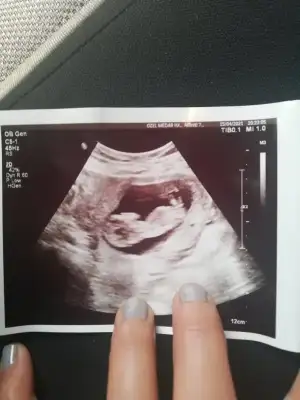

Kızlar selamlar, rica etsem bizim için de tahminde bulunur musunuz? Çok çok teşekkür ederim 💖😊

Tahminde bulunurmusun